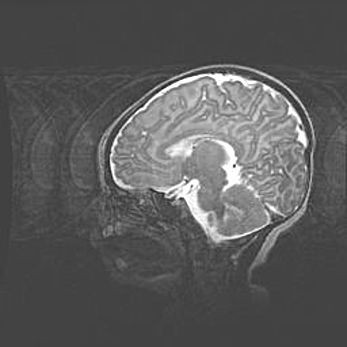

Мальформация Денди-Уокера. Киста задней черепной ямки.

Агенезия мозолистого тела.

Возраст: 2,5 месяца

Вес: 2420 г

Пол: женский

Окружность головы: 37 см

Срок гестации: 32 недели

Мальформация Денди—Уокера — редкий вид патологии ЦНС, представляющий собой врожденный порок развития каудального отдела ствола и червя мозжечка, ведущий к неполному раскрытию срединной (Мажанди) и латеральных (Лушка) апертур IV желудочка мозга. Для этогно синдрома характерна триада симптомов: гипотрофия червя мозжечка и/или полушарий мозжечка, кисты задней черепной ямки, гидроцефалия различной степени. В 70% случаев порок сочетается и с другими аномалиями головного мозга, в частности с агенезией мозолистого тела.